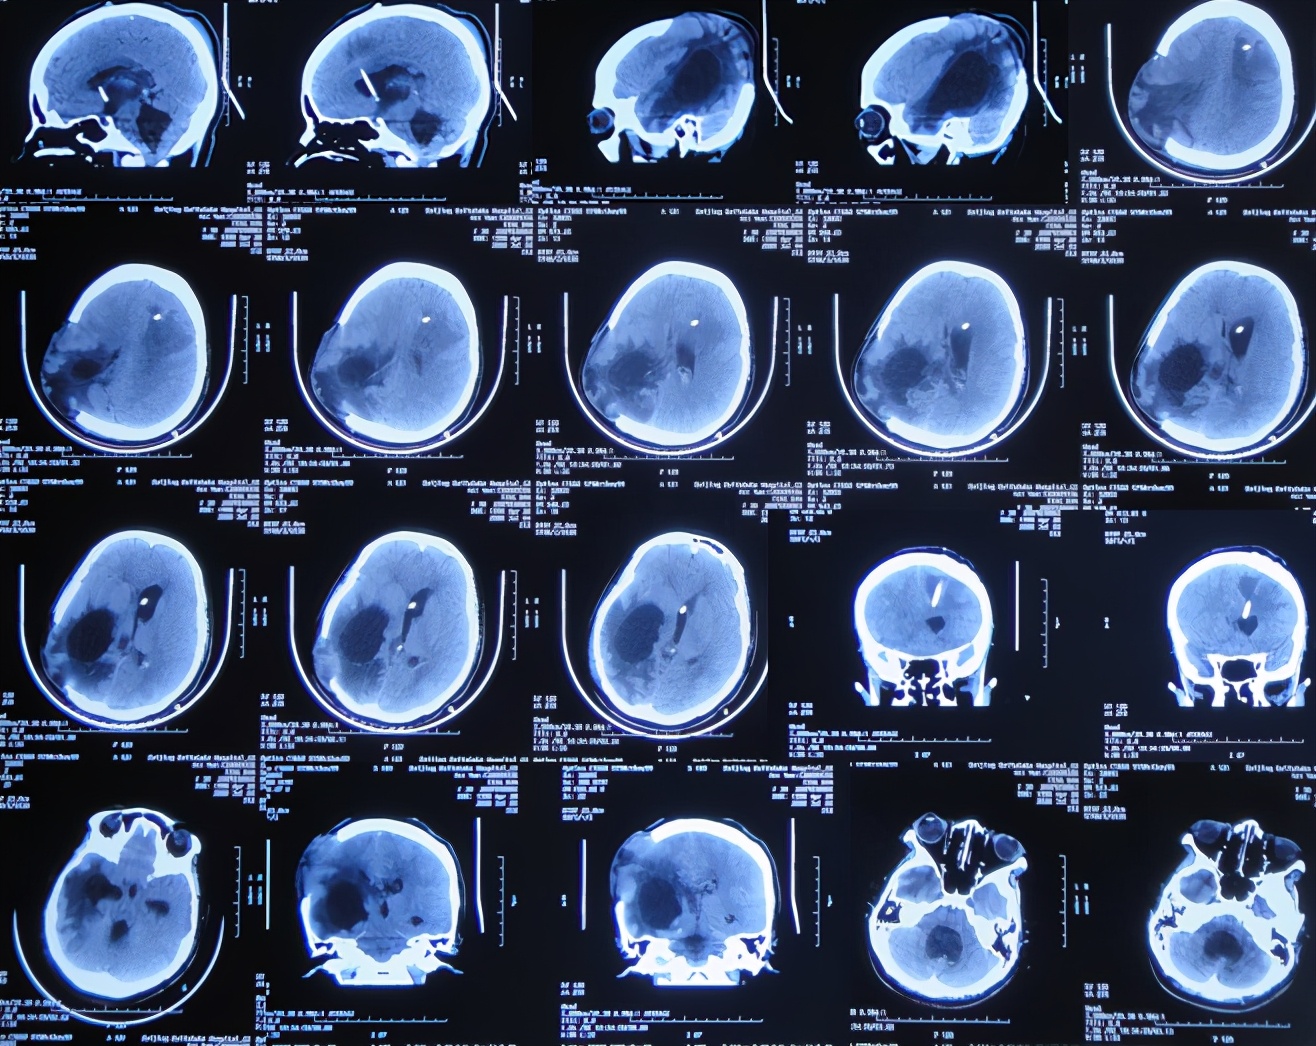

开颅术后15天即2020年4月17日(腰大池引流术后7天),查头颅CT示仍脑膨出( 图-4 ),因腰大池引流管堵塞,给予拔除并第2次重新置换腰大池。

图-4: 2020年4月17日头颅CT